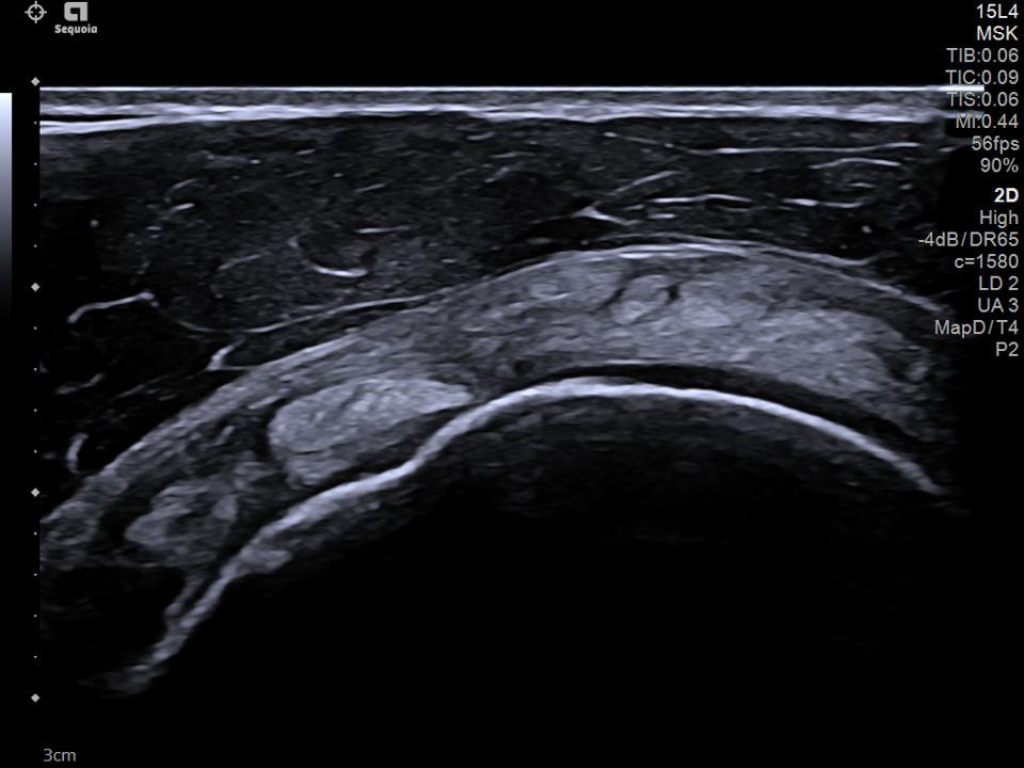

The latest updates on ACUSON Sequoia use the power of groundbreaking AI for abdominal cases, includes advanced breast visualization to deliver new levels of image quality confidence, and tackles the toughest challenges in musculoskeletal imaging, all while saving your team from needless strain and pain.

ACUSON Sequoia’s new advanced features are designed to improve diagnostic confidence and workflow across a wide range of clinical settings.

Boost your clinical confidence with a system designed to enhance your expertise. The ACUSON Sequoia gives you the power to know more by maximizing the sensitivity and depth of your scans, while reducing variability across patients, systems and users.

ACUSON Sequoia’s InFocus imaging architecture eliminates the need for conventional focal zones to create a fully focused image faster than conventional systems. Our InFocus technology applies to all imaging transducers and exam types giving you consistent imaging across clinical segments. Some of the benefits are:

- Improved spatial and contrast resolution

- Clear near field to far field

- High resolution imaging at high frame rates

- Next Gen 2D-SWE for greater sensitivity in detection and visualization of malignant breast lesions.